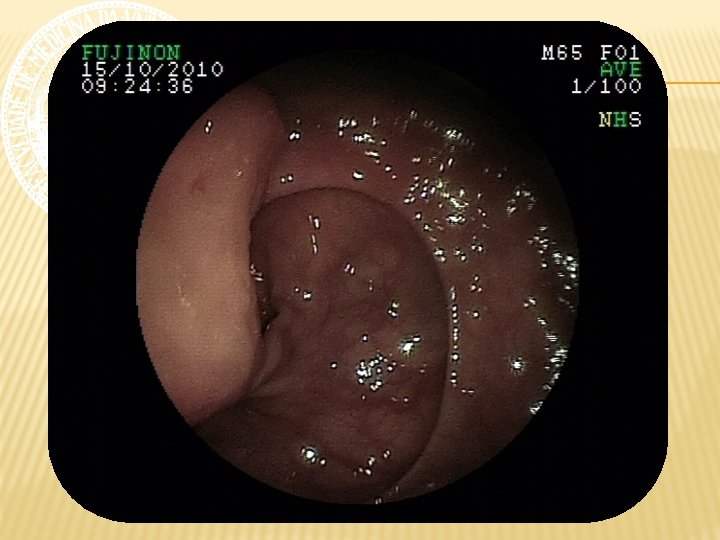

ENTEROSCOPIA RETRÓGRADA Nota-se em reto médio, a 15 cm da borda anal, LESÃO ELEVADA, pediculada, com superfície ulcerada, recoberta por fibrina e hematina, de aspecto subepitelial, medindo cerca de 4 cm de diâmetro. A 20 cm da borda anal, presença de ANASTOMOSE ileorretal, com algumas pequenas ulcerações, recobertas por delgada camada de fibrina, com fios de sutura, sem sinais de sangramento ativo e/ou recente. Íleo percorrido por cerca de 40 cm, não se observando alterações da mucosa. Realizada aplicação de endoloop, seguida de POLIPECTOMIA, sem intercorrências.

ENTEROSCOPIA RETRÓGRADA CONCLUSÃO 1. Colectomia total com ileorretoanastomose. 2. Ulcerações rasas em anastomose sem sinais de sangramento. 3. Lesão pediculada ulcerada em reto médio com sinais de sangramento recente. Polipectomia. 4. Íleo distal sem lesões.